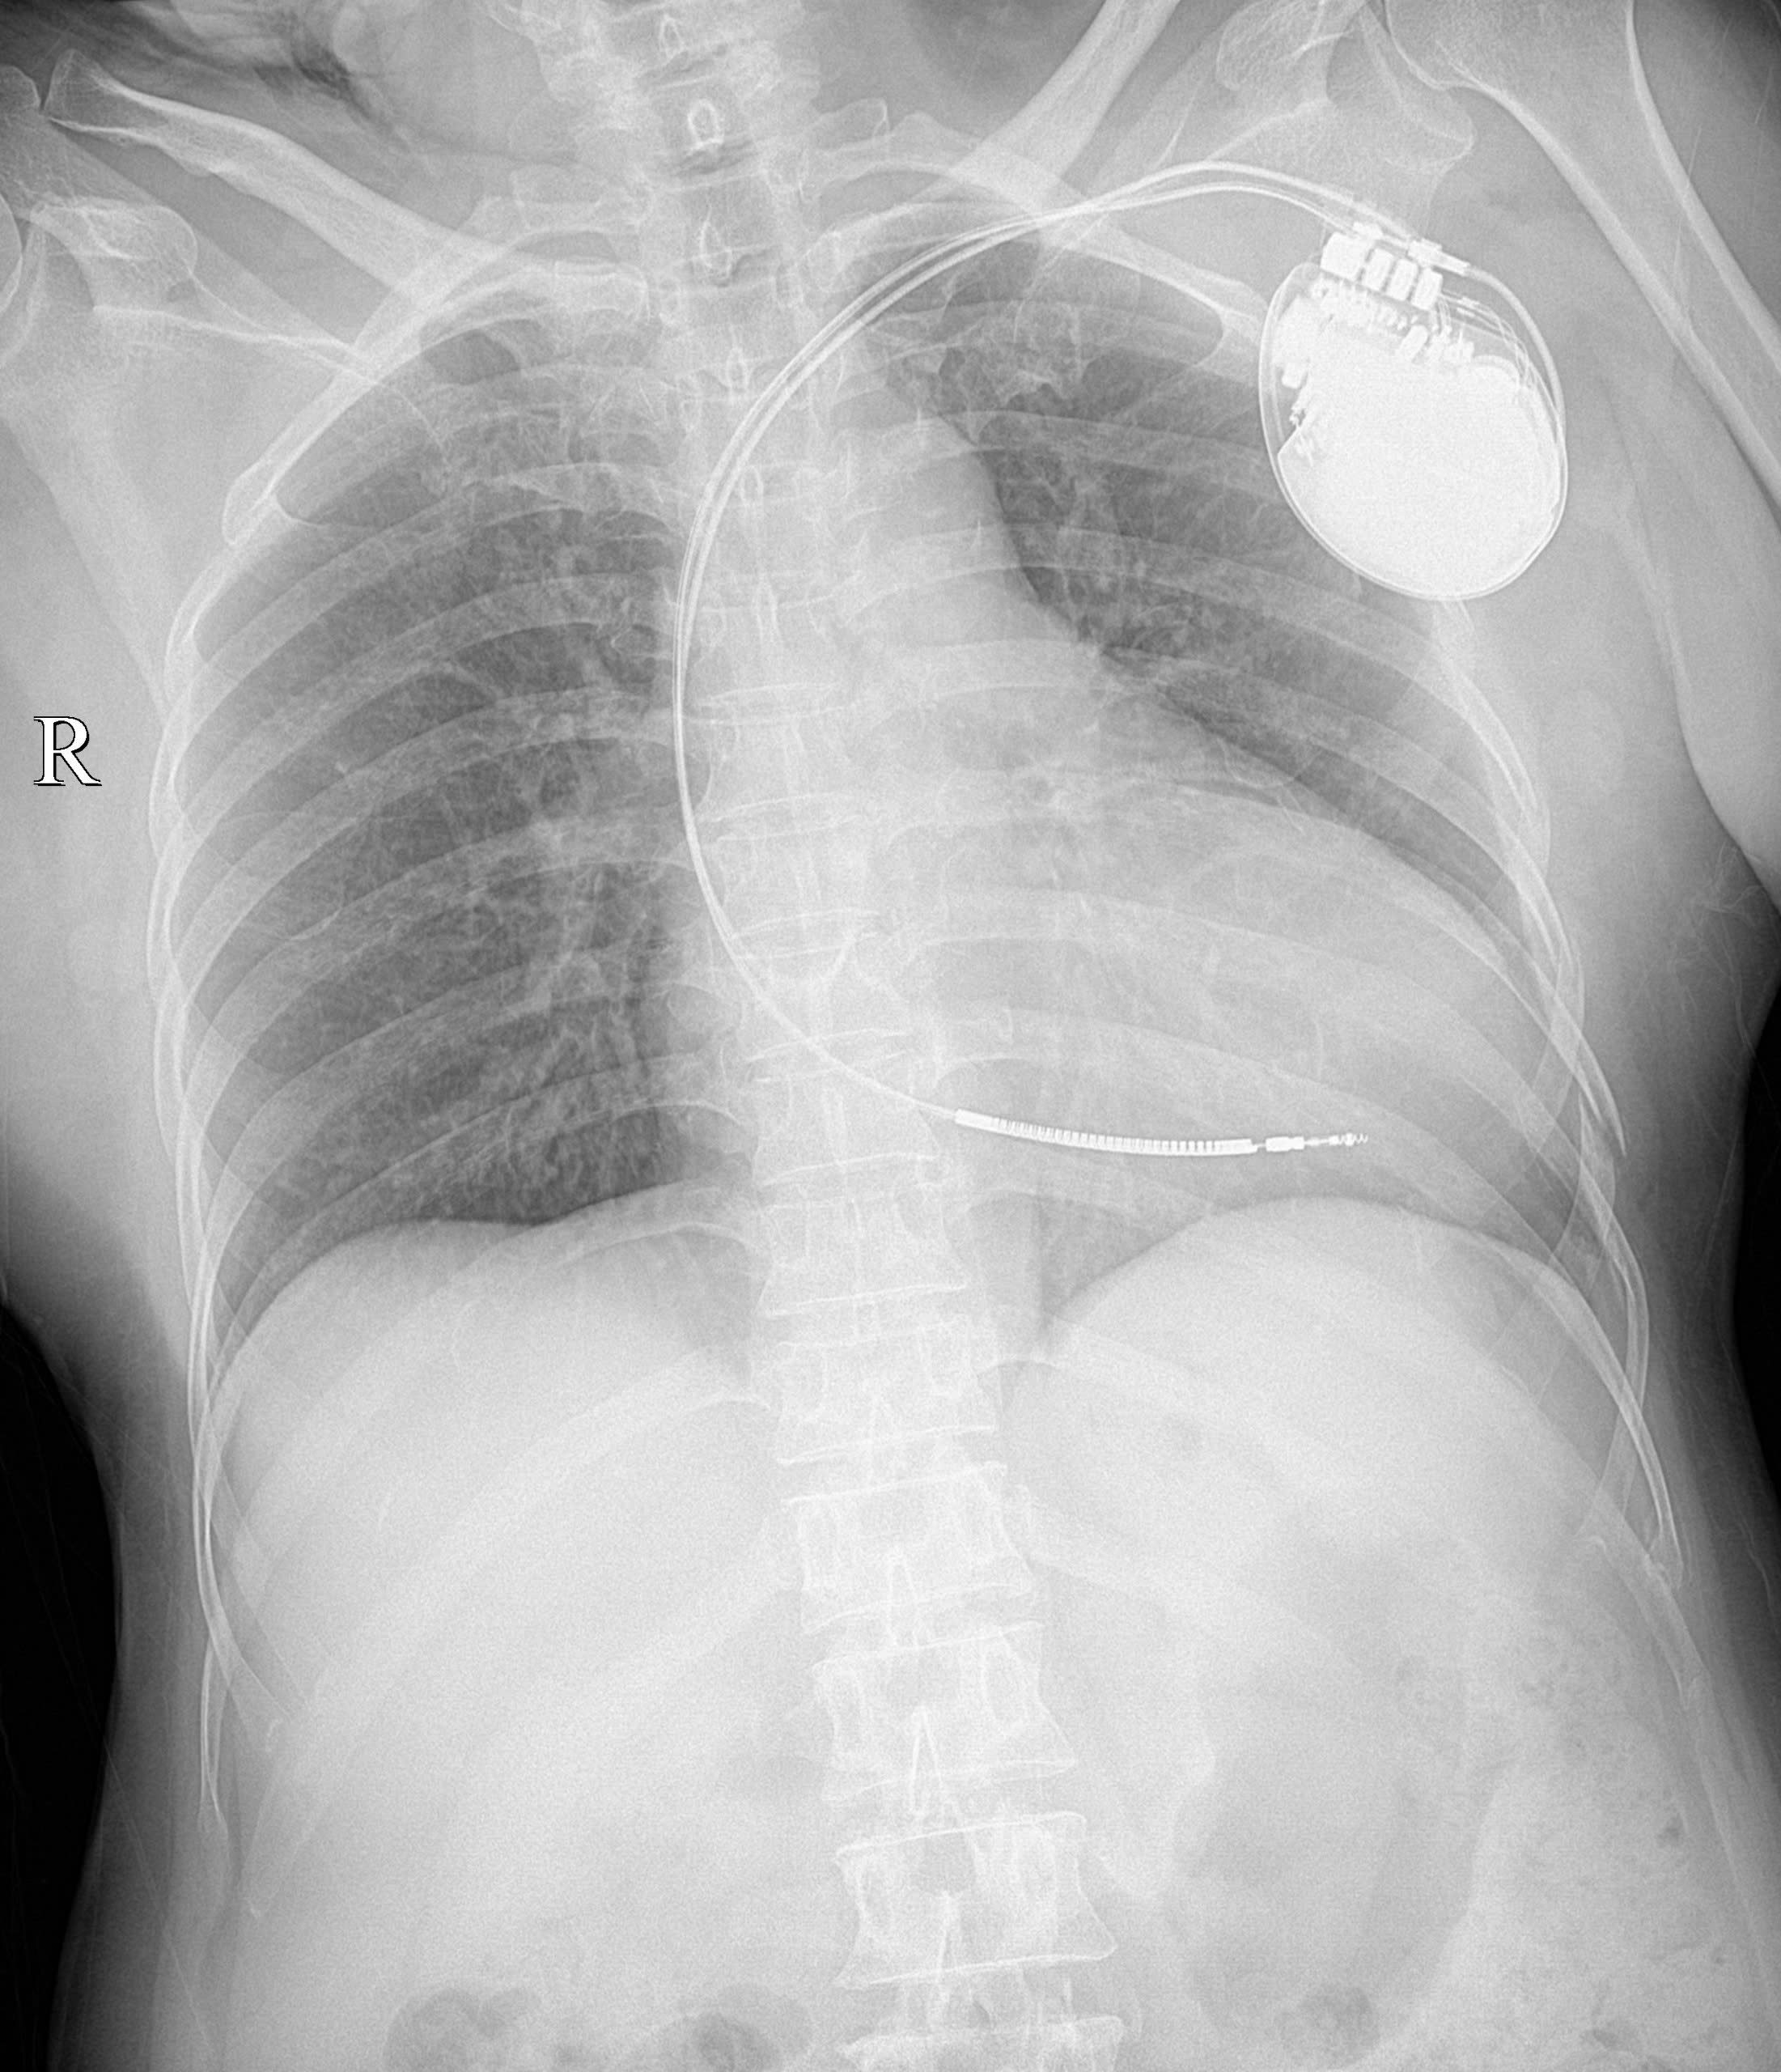

Ca can thiệp quan trọng này được thực hiện vào sáng ngày 27/11 trên hệ thống chụp mạch số hóa xóa nền DSA hiện đại của Bệnh viện. Quá trình thực hiện, các bác sĩ tạo đường vào mạch máu, đưa các điện cực vào buồng tim một cách chính xác. Sau đó, máy ICD được cấy vào và cài đặt để tối ưu hóa quá trình vận hành. Máy ICD hoạt động như một “vệ sĩ” 24/7, có khả năng nhận biết tự động các cơn rối loạn nhịp nguy hiểm. Khi phát hiện các cơn rối loạn nhịp nhanh như trường hợp bệnh nhân đang bị, máy sẽ lập tức tạo nhịp vượt tần số hoặc tự động sốc điện, chuyển nhịp ngay lập tức, ngăn chặn nguy cơ đột tử tim.

BSCKII. Dương Minh Tuấn, Trưởng khoa Can thiệp tim mạch, Trung tâm Tim mạch cho biết: Kỹ thuật cấy máy phá rung tự động được chỉ định trong các trường hợp người bệnh trước đó có ngừng tim hoặc rung thất, tim nhanh thất bền bỉ; người bệnh nguy cơ rung thất hoặc tim nhanh thất có tính chất gia đình; người bệnh nhồi máu cơ tim có phân số tổng máu thất trái dưới 35%; người bệnh suy tim có phân số tổng máu thất trái dưới 35% có độ NYHA II, III. Bác sĩ cũng khuyến cáo thêm, những người trong gia đình có người bị đột tử chưa rõ nguyên nhân hoặc bệnh nhân có tiền sử nhiều lần bị rối loạn nhịp tim, đã từng ngừng tuần hoàn, có tiền sử suy tim nên đến các cơ sở y tế chuyên sâu để được đánh giá và tư vấn phương án điều trị phù hợp nhất.